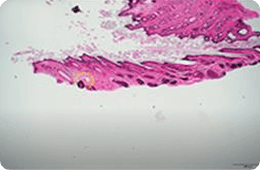

특히나 스컬피오의 532PS 핸드피스는 표피를 보존하면서

진피 내에서 LIOB를 생성하여 전통적인 532nm 레이저의 한계를 극복합니다.

532PS 핸드피스는 비침습적으로 진피에 도달하여, 피부 표면 손상 없이

진피층만 자극하여 노화된 피부 세포를 활성화 하고 빛나는 자신감을

만들어 줍니다.